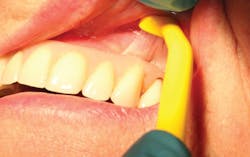

Interdental brushes

A staple for home care in all periodontal patients, the interdental brush (bottle brush; figure 10) is crucial for the care of implant embrasures, especially when they are wide. Unlike a natural tooth with a wide platform above the furcations, posterior implants have a wide tooth perched on a narrow post. This creates two nooks that invite both plaque to harbor and food to impact. A solution is to insert the widest interproximal brush that will comfortably fit in the space. The brush not only provides tissue stimulation but also removes plaque and debris instantly. Dipping the brush in an antiseptic increases the benefit.